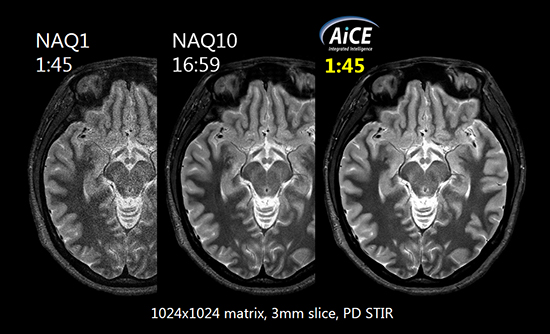

Advanced intelligent Clear-IQ Engine(AiCE)

ディープラーニングを用いて設計したSNR向上再構成技術により,高分解能画像においても短時間でSNRを確保できます。

Compressed SPEEDER

パラレルイメージング法と圧縮センシング法を組み合わせた高速撮像法により,画質劣化を抑えた高速化を実現します。さらにAiCEとの組み合わせにより高画質化と高速化を高い次元で両立します。